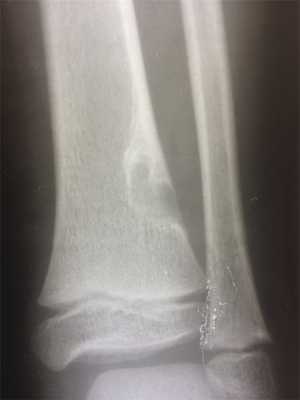

При рентгенологическом исследовании МФД выглядит как округлое или овальной формы литическое образование кортикального слоя (или субпериостально), чаще немного вытянутое параллельно оси кости. Границы четкие, как правило, хорошо заметна небольшая зона остеосклероза вокруг (рис. 3). По мере роста МФД начинает распространяться в медуллярном направлении. Поэтому НОФ всегда выглядит эксцентрично, но также с четкими границами и зоной перифокальных остеосклеротических изменений (рис. 4). При больших поражениях, занимающих более трети—половины поперечника кости, часто можно обнаружить дольчатость за счет склерозированных септ, в составе которых при гистологическом исследовании определяется фиброзная ткань с очагами реактивного остеогенеза. В данных случаях заболевание может манифестировать патологическим переломом. В редких случаях контуры НОФ могут выходить за анатомические пределы кости. Периостальная реакция в большинстве случаев отсутствует.

Рис. 4. Хорошо ограниченный очаг поражения дистального метафиза большеберцовой кости с выраженным перифокальным склерозом, больше выраженным в области диафизарного полюса образования. Стадия D по Ritschl.